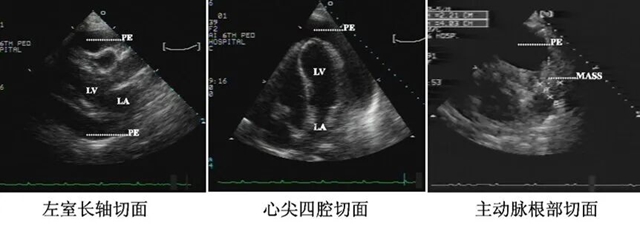

心脏彩超主要是看心脏结构的,一般不容易诊断冠心病。

冠状动脉CT/冠状动脉造影,二者都是通过在冠状动脉内注入造影剂,借助X透视的指导从而了解供应心脏血管是否有堵塞,冠状动脉的通畅程度,是诊断冠心病的金标准。

同一患者心电图、心脏彩超、冠脉造影对比图